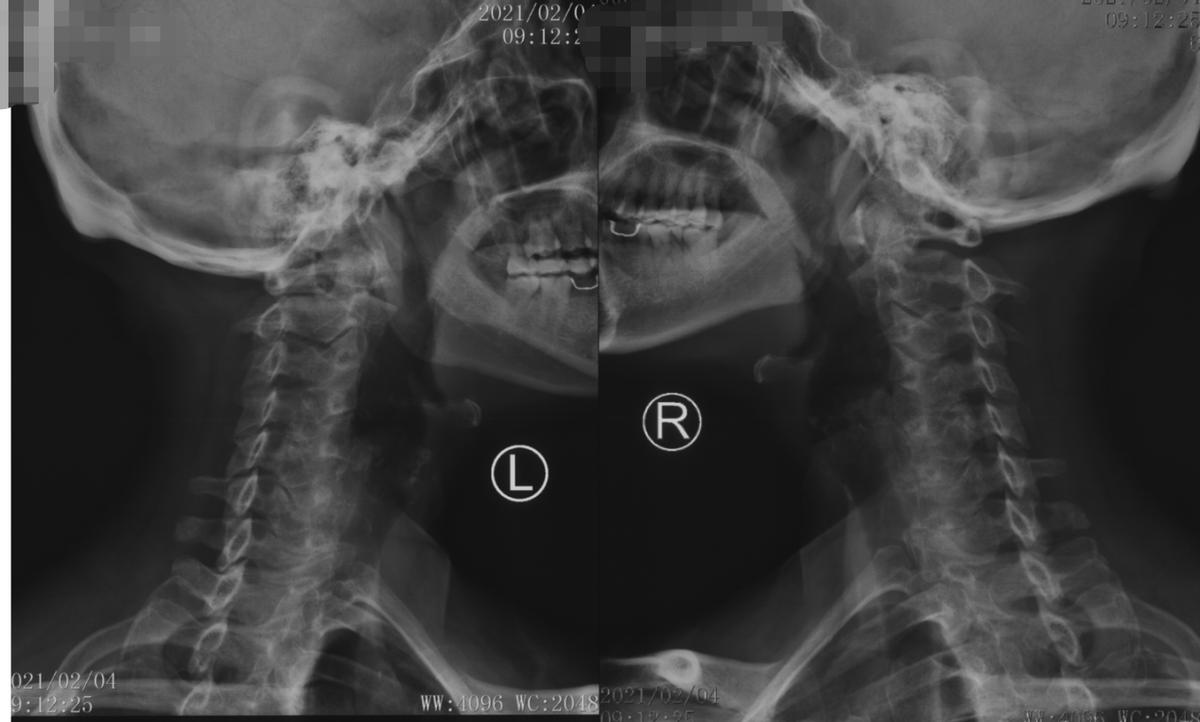

接诊了黄女士后,我为她做了详细的查体,并建议进行颈部的影像学检查。综合各项检查结果发现,原来是黄女士的颈椎出现了问题,她之所以出现这些症状是由于颈椎间盘突出造成了神经根压迫,为神经根型颈椎病。而且黄女士的情况比较严重,多个节段都出现了颈椎间突出,包括颈3/4、颈4/5、颈5/6。此外,还有后纵韧带骨化、颈椎管狭窄。这种情况,我建议黄女士进行手术治疗,将突出的椎间盘髓核切掉,并给神经充分减压。

术前x线片